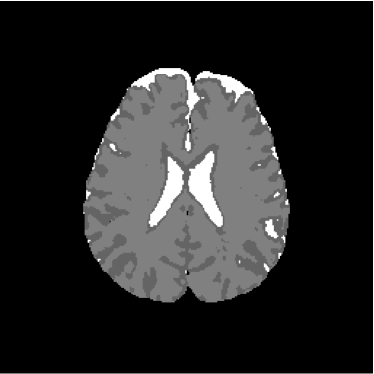

To evaluate objectively the classification results, there were used three methods: the index κ𝜅\kappa, the overall accuracy and the confusion matrix. The subjective evaluation was performed by the specialist knowledge of a pathologist. Image background (C3subscript𝐶3C_{3}), gray and white matter (C2subscript𝐶2C_{2}) and cerebrospinal fluid (C1subscript𝐶1C_{1}) were associated to the colors white, gray and black, respectively.

Figure 13 shows the training set mounted on the 13th slice of the volume of ADC maps. Figures 14 and 15 show the ground truth volume and the 13th slice, respectively.

Refer to caption

Figure 14: Ground truth image (13th slice) generated by polynomial net classification

Consequently, the measured similarities between the results obtained by the use of 4-degree and 3-degree polynomial classification related to the 2-degree classification were 0.9816 and 0.9904, respectively. Therefore, we have chosen the result obtained by the 2-degree polynomial classification.